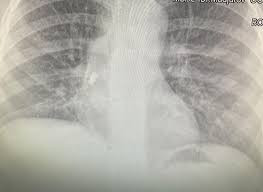

След известно време синът й започва да вдига температура, лекуван е с антибиотици, но температурата продължава. Личният лекар назначава рентгеново изследване и на снимката се вижда зъбът. От него се е развила инфекция на дихателните пътища, което обяснява повишената температура.